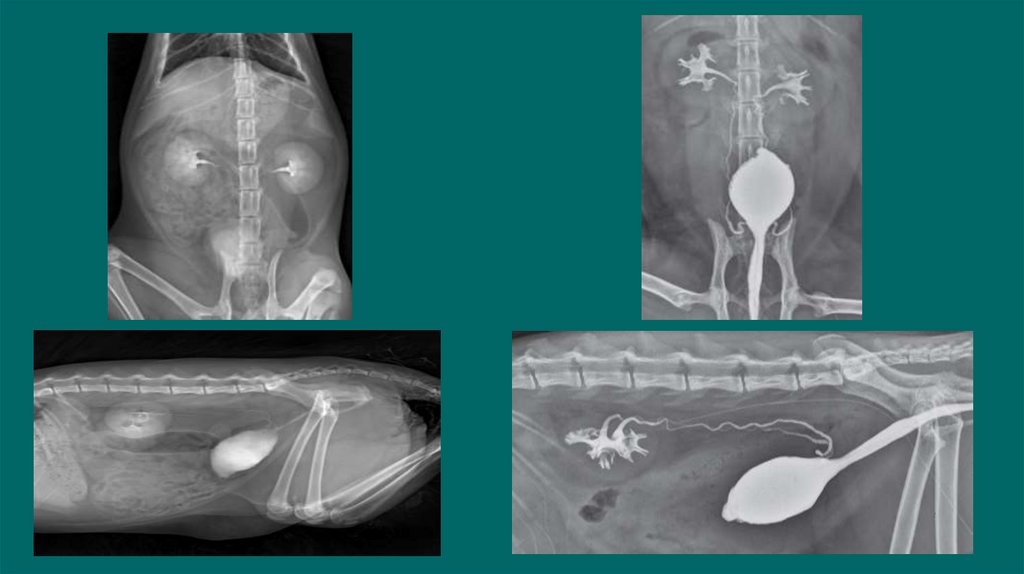

40. Экскреторная урография

Рентгенологическое исследование с внутривенным введением контраста .

Показания:

Субъективно функцию почек СКФ, пиелоэктазию, гидронефроз, оценить проходимость

мочеточников, обнаружение эктопии мочеточников ,обнаружении разрывов на уровне от

мочеточников до мочевого пузыря

Подготовка пациента:

1.Голодная диета 12-24 ч, при необходимости очистительная клизма.

2.Стабильная гемодинамика

3.Установка в/в катетера/Инфузия

4.При необходимости под седацией

Техника

Получение обзорных боковых и ВД снимков (важно отсутствия каловых масс

Введение йодсодержащего контраста в дозе 400-800мг/кг йода(Омнипак,Урографин) в/в болюсно

Получаем латеральные и ВД снимки сразу после введения контраста ,а затем через 5,20, и 40 минут

Для обнаружения эктопии мочеточника могут быть использованы косые снимки

Рекомендован в/в ведение жидкостей в момент или после для поддержания гидратации и индукции диуреза.

42. Пиелография

Определения локализации обструкции мочеточников у кошек с азотемией

Снижен риск попадания контраста в почки при нефропатии

Проводится под УЗИ контролем.

Тонкоигольная аспирация содержимого из лоханки(пиелоцентез)

Спинальной иглой или иглой диаметром 22G вводят под углом 45

Введение йодсодержащего контраста йода(Омнипак,Урографин)

Объем контрастного вещества должен составлять половину объема аспирационной мочи

Dominique Penninck, Marc-Andre d Anjou.2008-2015